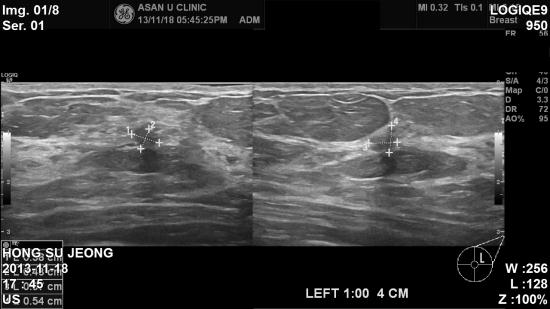

아산유외과 개원후 39번째 유방암진단.

우측유방암으로 수술 예정인 분으로

수술전 검사인 유방 MRI 를 통해 좌측 유방에도 0.6cm의 결절이 보여

본원에 의뢰되어 조직검사로 침윤성 유방암이 진단되었습니다.

우측 유방과 좌측 유방에 암을 동시에 수술해야하는 경우가 된 것입니다.

유방초음파를 통해 유방암을 찾지만

유방 MRI의 효용성은 비싼만큼 그값을 톡톡히 합니다.